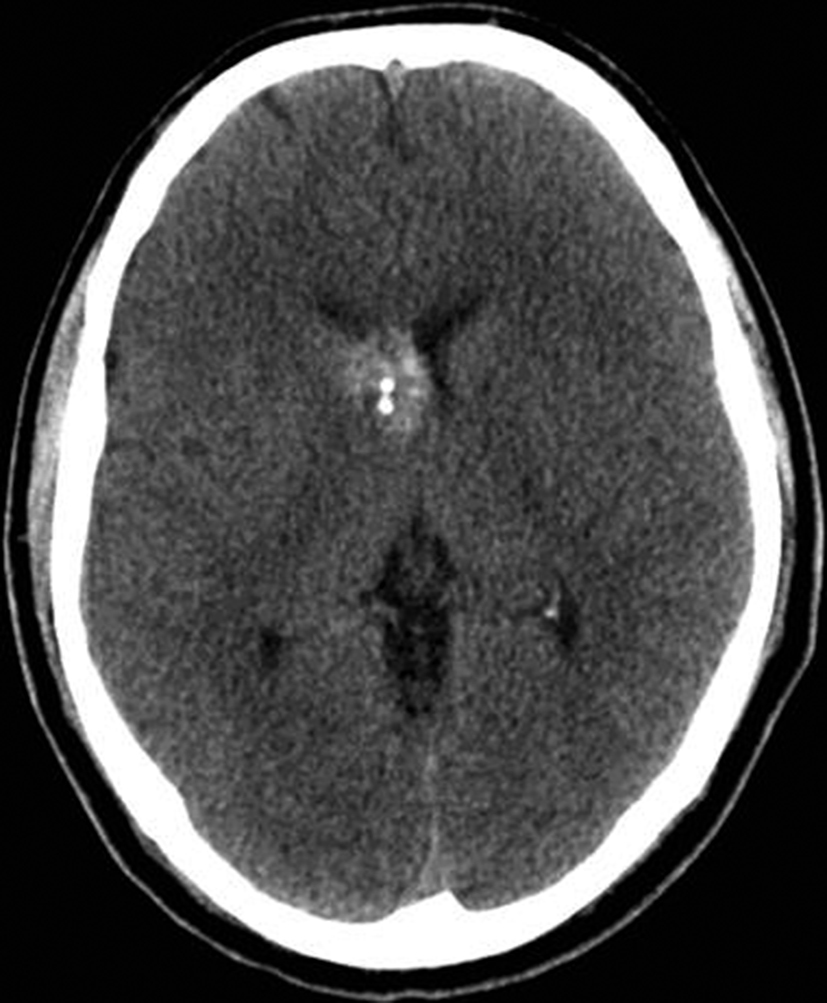

Con los hallazgos tomográficos, no se efectúan planteos diagnósticos y se realiza una resonancia magnética con la finalidad de obtener más datos semiológicos en busca de una aproximación diagnóstica. Se realizó el estudio por medio de secuencias T 1, FSE T 2, FLAIR, SWI y Difusión, en cortes axiales, FSE coronal y sagital T 1. Se realiza la administración de gadolinio DTPA en los tres planos. Se evidencia la lesión bien definida a nivel del ventrículo lateral derecho, que involucra al tronco del cuerpo calloso (Figura 2- C y 3- B). Presenta intensidad de señal heterogénea en secuencias T1 y T2 (Figura 3 y Figura 4). En secuencia ecogradiente se observa una señal marcadamente hipointensa y heterogénea, con un halo hipointenso bien definido (Figura 2- C). No presenta realce significativo tras la administración de Gadolinio (Figura 2- B) y en la secuencia de difusión no presenta restricción.

Se efectúa un control imagenológico al año del diagnóstico mediante una TC sin y con contraste (Figura 5 – A y B), donde se evidencia la lesión sin cambios significativos en cuanto a su tamaño y características.

Figura 2 Resonancia magnética.

a) Imagen axial T1, lesión intraventricular con intensidad de señal heterogénea.

b) Tras la administración de Gadolinio no presenta realce significativo.

c) Imagen axial en secuencia ecogradiente donde se evidencia la lesión hipointensa y heterogénea. Se observa la extensión de la lesión al cuerpo calloso.

a y b) Cortes axiales de TC sin y con contraste intravenoso. Control tomográfico al año del estudio inicial, no se observan cambios significativos de la lesión.